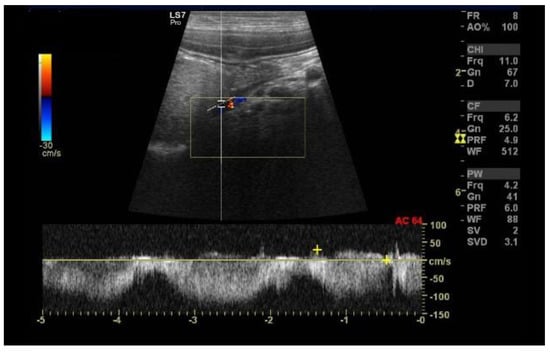

6.5. Portal Vein Blood Flow

6.6. Portal Vein Tributaries